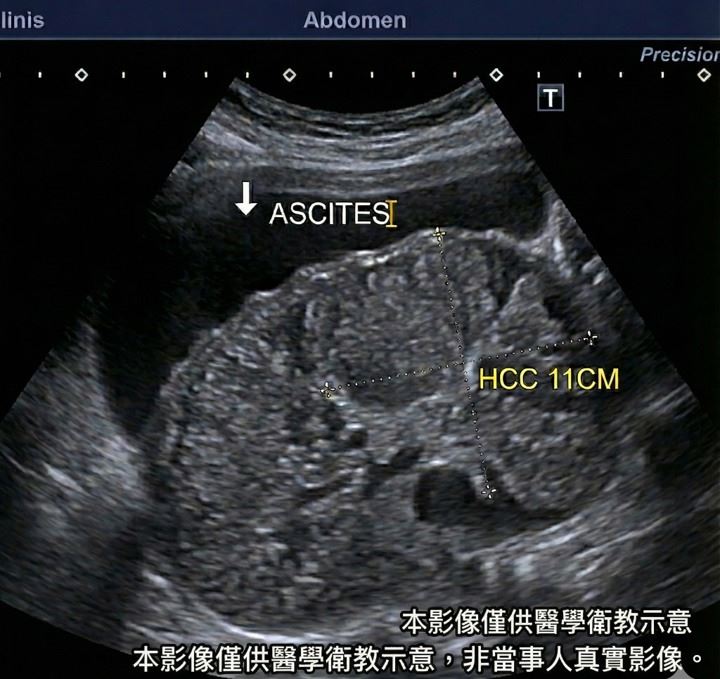

一名40歲男性近日因腹部脹大、感覺不適前往門診就醫,自述只是想拿些消脹氣藥物,未料檢查結果卻令人震驚。雲林長庚醫院肝膽胃腸科醫師卓韋儒指出,該名病患腹部膨大並非腸胃脹氣,而是腹腔內已累積大量腹水,進一步超音波檢查發現,患者不僅出現嚴重肝硬化,肝臟內更有一顆直徑達11公分的巨大肝腫瘤。

卓韋儒在粉專「卓韋儒醫師|內視鏡專科・肝膽胃腸」發文,當天他門診有一位40歲男病患想要拿點消脹氣藥回去,不過經過面診後,卓韋儒認為該名男子臉色不對,肚子大得不自然,於是就拉去超音波室一掃,怎料根本不是脹氣,而是滿肚子的腹水,且影像底下,是嚴重的肝硬化,還有一顆11公分的巨大肝腫瘤。

卓韋儒提到,當下氣氛瞬間安靜了,也給所有人嚴肅提醒「肝臟沒有痛覺,等到它把肚子撐到讓你覺得『脹』,往往都已經是晚期」,不要自己當醫生,以為肚子大就是變胖,特別是B、C肝帶原者,每半年的超音波,絕對不能省。